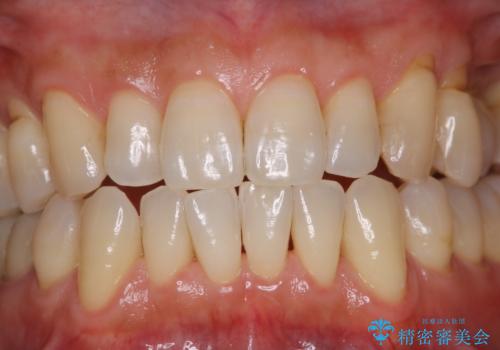

- PMTCでのメンテナンスを定期的に行っている方です。PMTC30分コースを行いました。

日々の磨き残しなどをそのまま放置すると、細菌が固まり硬い歯石になります。

歯石になってしまうと、とても硬く、歯ブラシで取り除くことが出来なくなります。

よって、歯科衛生士による専門的なクリーニングを定期的に行うことがとても大切です。

メンテナンスの間隔は個人差がありますが、基本的には2~3カ月に一度行うことをおすすめしています。